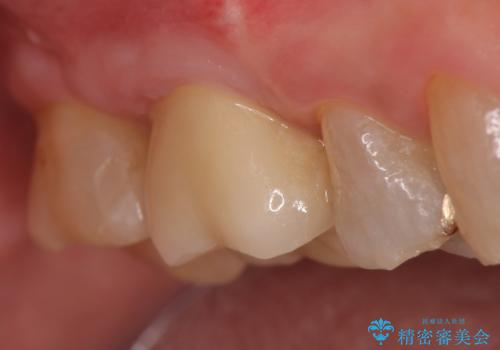

オールセラミッククラウン・セラミックインレー 歯茎より深い虫歯の治療

- 冷たいものがしみる右上の奥歯を治療して欲しいといらっしゃった方の症例です。

その後歯茎の回復を待ち、オールセラミッククラウンおよびセラミックインレーによる補綴・修復を行いました。

オールセラミッククラウンについて

今回用いたオールセラミッククラウンはジルコニアフレームという白い素材の上にセラミックを盛っているため、審美性が非常に高いのが特徴です。

また、ジルコニアは人工ダイヤモンドの材料にも使われているほど高い強度を持っており、そのためオールセラミッククラウンは審美性だけでなく、奥歯やブリッジの補綴も可能とするクラウンです。